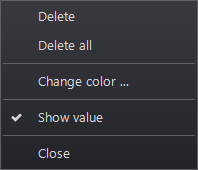

Kattintson jobb gombbal a kép annotációra

A megnyíló ablakban két lehetőség van: Törlés vagy Miden törlése. A többi opció az annotációtól függően módosításokat tesz lehetővé, beleértve a szín és betűtípus változtatásait is.